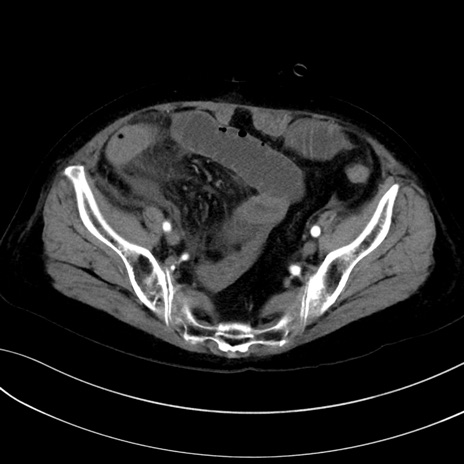

症例13 CT(横断像)1日半後